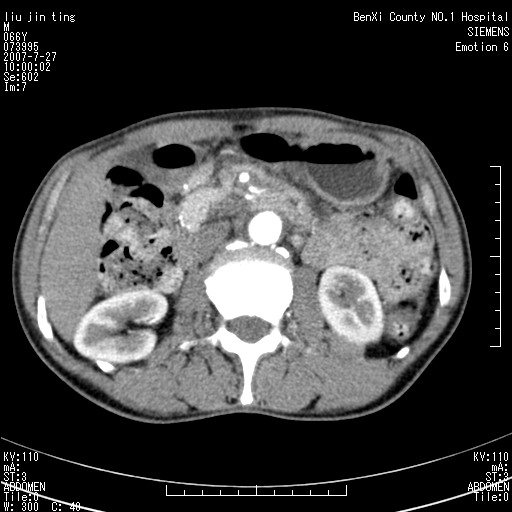

腹痛,背痛,无恶心呕吐,不黄,彩超示胰腺钩癌,ct扫描病灶平扫30-40hu,增强后动脉期40--60hu,静脉期50-68hu,真的是钩突上的么?您要试一试么?

动脉期

静脉期

沿着肠系膜上动脉呈匍匐性生长的软组织肿块,形态不规则,包绕肠系膜上动脉,呈明显强化,考虑来源于肠系膜的恶性肿瘤

沿着肠系膜上动脉呈匍匐性生长的软组织肿块,形态不规则,包绕肠系膜上动脉,呈轻-中度强化,考虑来源于肠系膜的恶性肿瘤。

钩突是正常的,只见腹膜后淋巴结的肿大,考虑淋巴瘤或转移可能。

支持!恶性纤维组织细胞瘤可能,与淋巴瘤及淋巴结转移鉴别(腹主动脉周围清晰,其他部位亦未见明显肿大淋巴结)。